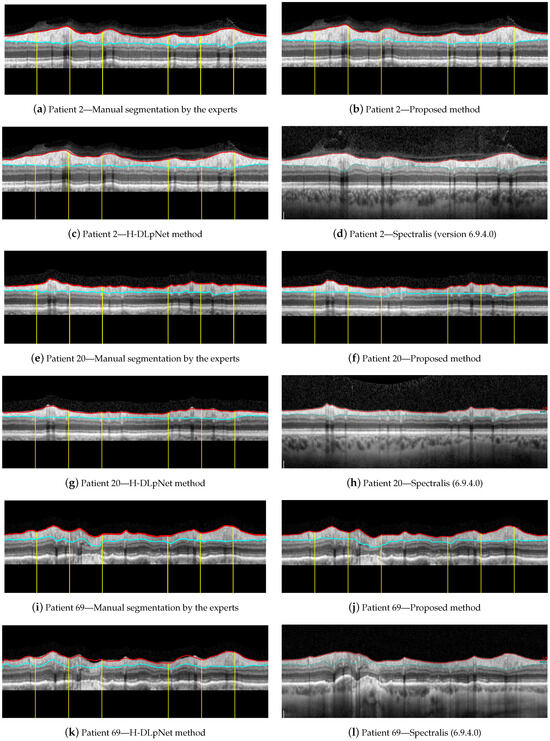

For illustrative purposes, Figure 15 shows a qualitative assessment of the RNFL segmentation provided by the manual delineation of the ophthalmologist, the proposed approach, the H-DLpNet method and the commercial software of the Spectralis OCT device. These three examples of representative OCT images were arbitrarily chosen for this evaluation, namely the right eye of patients 2, 20, and 69 from the database. Note that only the ground truth of these three cases is available since the manual segmentation of the experts is time consuming and cost expensive. As discussed in Section 4, the manual segmentation of the entire database will be carried out as a future work to provide a trustworthy ground truth.

Figure 15.

Segmentation results for the right eye of (a–d) patient 2, (e–h) patient 20, and (i–l) patient 69.

By first applying a qualitative analysis to the results depicted in Figure 15, we can clearly see that the three methods handle the delineation of the upper boundary of the RNFL with adequate reliability. However, it can be noticed that the H-DLpNet method tends to generate excessive smoothing in bumpy areas, with peaks and valleys, causing certain inaccuracies. By contrast, both the proposed method and Spectralis tend to produce a result closer to the manual segmentation as defined by the experts.

The analysis of the accuracy of the lower boundary of the RNFL is, on the other hand, notoriously difficult. As described in Section 2.1, the speckle noise and the artifacts due to the shadows cast by blood vessels generate inaccuracies in all the segmentation algorithms. However, this lack of information in the shaded areas is also a challenge in the manual segmentation carried out by the experts. This makes it unclear which method shows a higher precision in certain images of the database.

Analyzing the manual segmentations in Figure 15, it can be observed that the H-DLpNet method tends to project upward the layer delineation inside the areas shaded by the vessels, while Spectralist tends to project the layer in the downward direction. The proposed method, on the other hand, tends to be a compromised solution by maintaining a greater continuity of the layer in these areas. In manual segmentation, experts maintain or lower the location of the lower edge in the shaded areas, as roughly performed by the proposed method and Spectralis, respectively. Note that although only three OCT images are shown in these figures, similar results can be observed in most of the images in the database. This inaccuracy in the shaded areas, even for the experts, complicates the quantitative analysis whose metrics are detailed in Section 3.